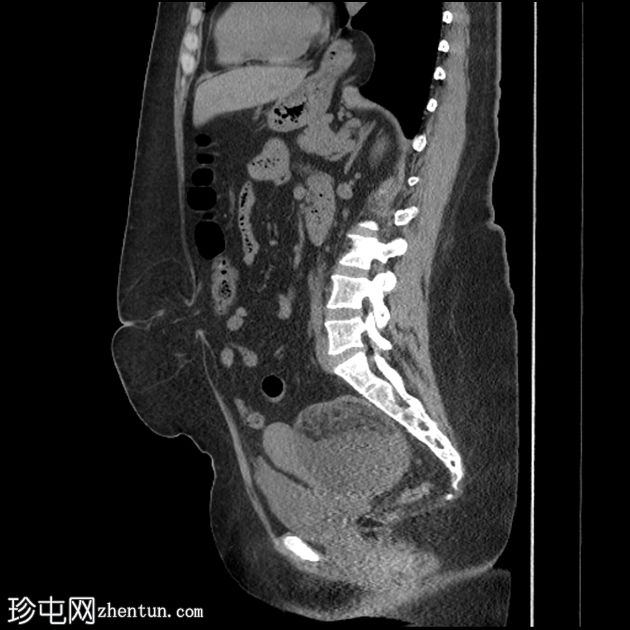

矢状位

T1加权像

盆腔可见部分囊性肿块,内含脂肪球。